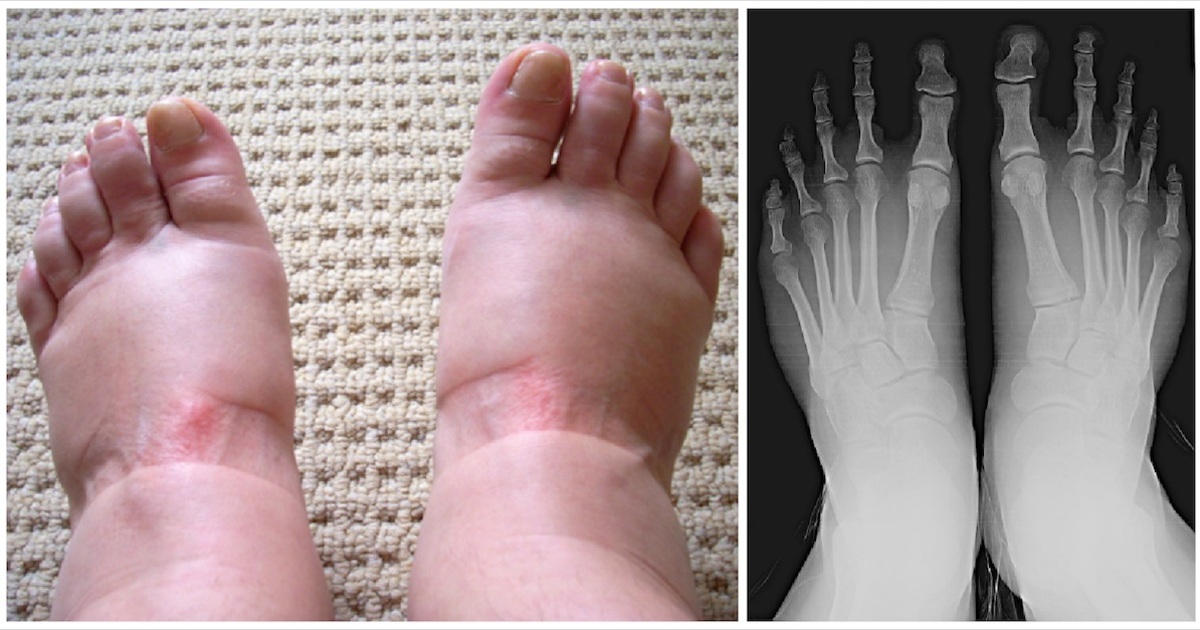

Inflammatory conditions are another major category. Arthritis, such as osteoarthritis or the more severe rheumatoid arthritis, can cause joint swelling, pain, and stiffness in the hands and feet. Gout, another form of inflammatory arthritis, often strikes suddenly at night, causing intense pain, redness, and swelling, typically in the big toe. Infections like cellulitis also cause noticeable swelling, making the skin feel hot and tender to the touch.